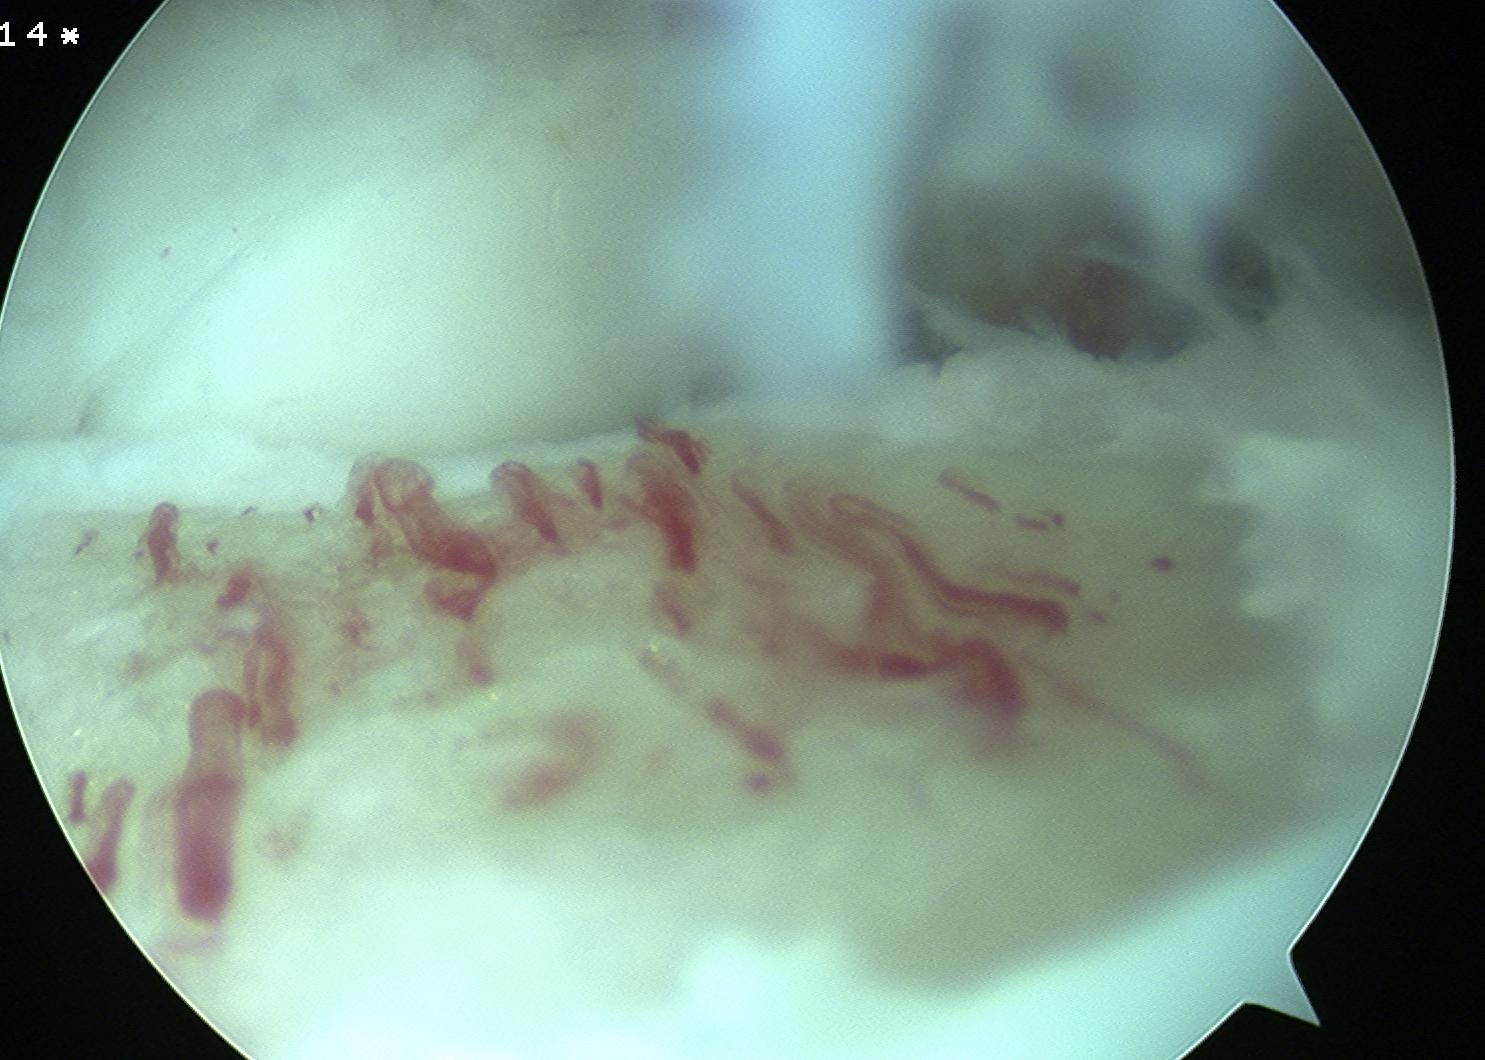

Arthroscopy techniques microfracture talus

Arthroscopy techniques AMIC talus

Arthroscopic techniques minced cartilage talus